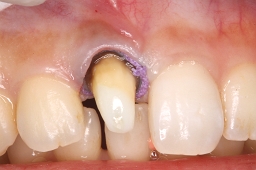

写真(形成中)のように歯茎をよけながら凸凹してないか、

マイクロスコープで丁寧に確認していきます。